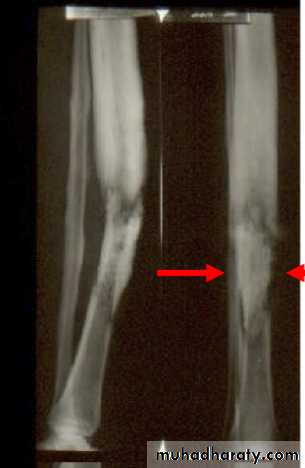

Imaging: X-Ray:

For the first 10 days no bone abnormalities, only soft tissue swelling. Later there is rarefaction of the metaphysis and periosteal new bone formation. With healing there is sclerosis. Sometimes there are sequestra separates from the surrounding bone by radiolucent line.Bone scintography: Shows osteoblastic activity, it is used for. Localization of pathologic process to anatomic area at earlier stage. Also useful for finding out polyostotic lesions especially in neonate